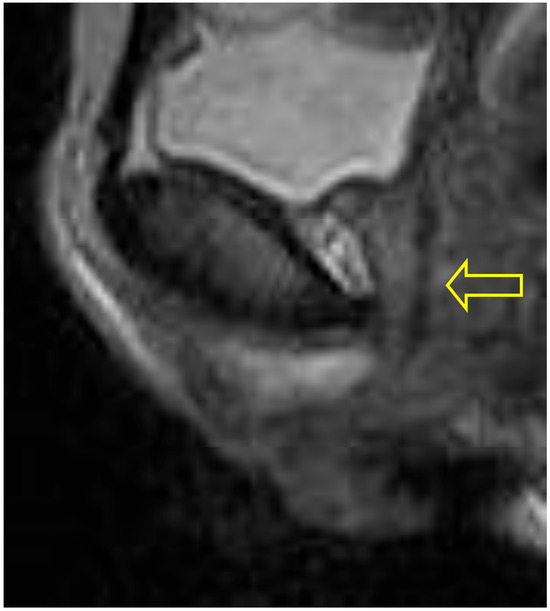

In the supine bridge pose (Setu Bandha Sarvangasana), the axial images show an oval shape of the urethra beginning just below the bladder neck which continues to be evident at the mid-urethra (see Figure 5). In addition, narrowing was evident in the mid-urethra in sagittal scans (see Figure 6); when measurements were compared to supine baseline images where the mid-urethra measured 12 mm, the supine bridge pose measurement was 8 mm. Comparison with standing posture images also suggested an increase in urethral length during the supine bridge pose, with a change from a baseline of 36 mm to 45 mm (Figure 7).

Figure 6. Supine bridge pose: This sagittal scan illustrates a view where the entirety of the course of the urethra can be visualized, and a narrowing is evident at the mid-urethra (lower arrow). The bladder neck is identified by the upper arrow and did not change in diameter or volume from supine to bridge pose.

Figure 7. Supine scan: This resting supine scan provides comparison with the supine bridge pose scan shown in Figure 6. In supine imaging the anatomic outline of the urethra (indicated by arrow) shows no regional narrowing.